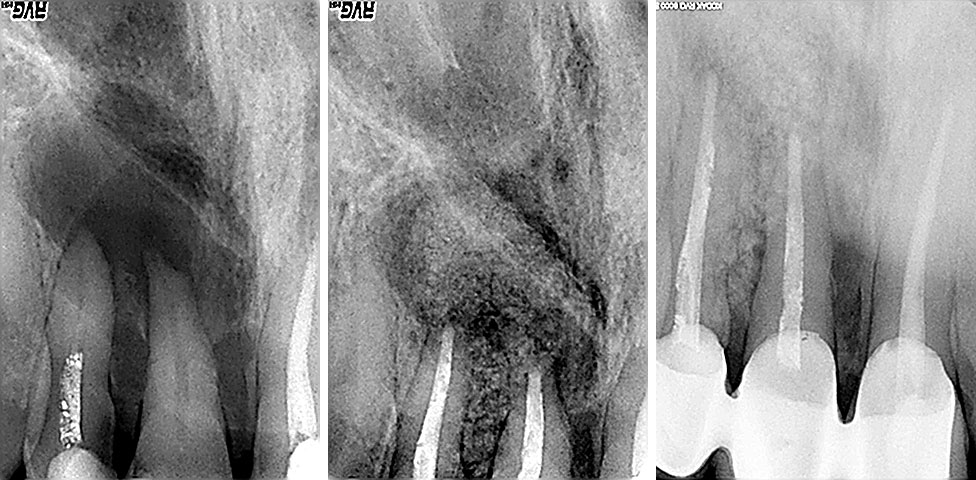

Parodontologija